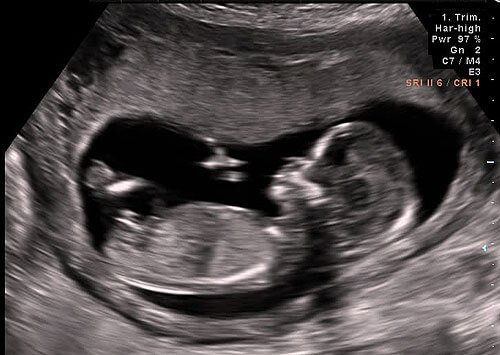

Ultrasound Exam

The world technology is developing at a rapid pace and new things are invented to the world on a regular basis and that applies for baby gender prediction as well. Ultrasound exams (Sonograms) are a good example of this scenario. Ultrasound is the most widely used technique nowadays, for knowing the sex of the fetus, as it is safe and very accurate.